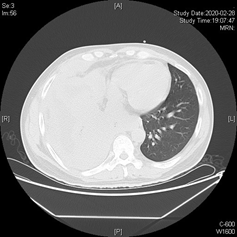

今年3月份,已经持续发热伴咳嗽将近2月有余的小张,曾被其他医院诊断为转移性肺低分化腺癌,已到晚期,但小张接受传统化疗后,发热、咳嗽、气促等症状仍没有改善,他抱着最后一丝希望辗转就诊我院。

入院后,呼吸与危重症医学科医师们综合分析病情,认为治疗的突破点应该是积极寻找可能存在的肺癌驱动基因,再次选择合适的病灶部位进行肺穿刺活检是关键。

在肺癌一体化诊疗模式下,放射科、病理科等相关的多学科专家很快就汇集一堂,共同探讨患者病情,最终确定最佳活检部位,最佳基因检测方法及范围,难题迎刃而解!根据新的基因检测报告,呼吸与危重症医学科医师们重新做出诊断,为右下肺腺癌,小张接受新的靶向药物治疗后体温即降至正常,咳出灰白色坏死物,咳嗽、气促减轻,家属激动的说:将近2个多月来,终于听他说想要吃一些好吃的!太感谢医生们了!

1月后复查胸部CT,肺部病灶及胸膜病灶显著缩小,现患者病情已改善出院。